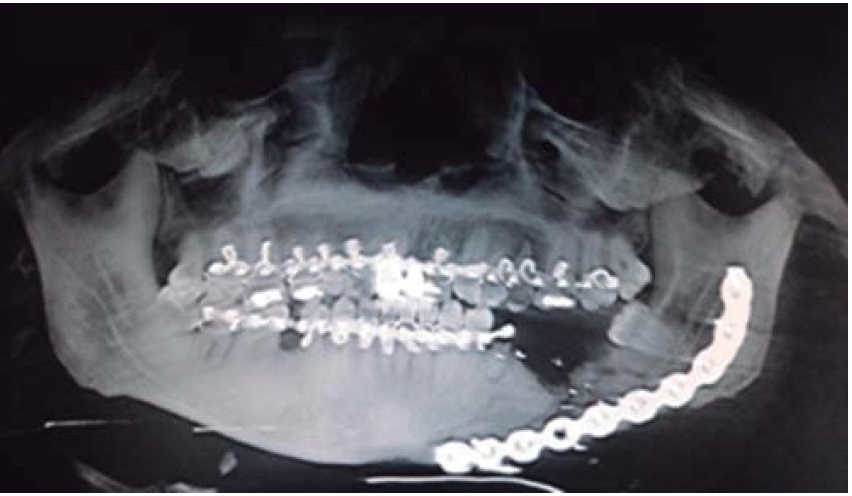

Se inicia tratamiento terapéutico de inmunización, antibioticoterapia, analgesia, extracción de focos sépticos y lavados mecánicos de la herida. La paciente no cuenta con prótesis ni parcial ni removible por lo que para establecer la relación intermaxilar y altura facial se confeccionan férulas de Gunning (Figura 13). A los diez días del tratamiento inicial se encuentra con adecuada cicatrización a nivel alveolar, con presencia de secreción no fétida a nivel de herida mandibular y se procede a realizar el segundo procedimiento mediante un abordaje extraoral con una placa de reconstrucción mandibular 2.4 y una placa 2.0 para un segmento óseo (Figuras 14 y 15). Se otorga el alta, acude a valoraciones periódicas con buena cicatrización (Figura 16), y adecuada movilidad mandibular. A las tres semanas posteriores a la reconstrucción se indica a la paciente iniciar tratamiento protésico para su rehabilitación.

En los tres casos presentados se inicia con valoración cardiopulmonar, manejo de vía aérea, control hemodinámico, ventilación, discapacidad neurológica y daños específicos.9-11 Con la exploración física determinamos la extensión de daño en los tejidos, presencia de orificios de entrada y salida para descartar la presencia de bala al interior en una cavidad o tejido (caso 2). El manejo maxilofacial se inicia con desbridaje conservador, lavado, extracción de restos radiculares, sutura y estabilización oclusal. La reducción y fijación de las fracturas (caso 1 y 3) se realizó en un segundo acto quirúrgico con placas de reconstrucción. En los casos expuestos se observó una buena evolución, una cicatriz ósea favorable y la necesidad de continuar con una rehabilitación oral mediante prótesis o implantes osteointegrados. Las complicaciones y secuelas son comunes y surgen por lo general a causa de la severidad de las lesiones iniciales, retraso en el tratamiento por riesgo vital o estado sistémico del paciente.